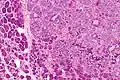

| Micrograph of an epithelial-myoepithelial carcinoma (right of image). The epithelial component has a tubular morphology and is evident only focally (upper left of image). Benign serous glands (parotid salivary gland) are also seen (left of image). H&E stain. | |

This tumour is characterised by biphasic tubular structures composed of inner ductal and outer clear myoepithelial cells.

Its appearance is very similar to adenomyoepithelioma of the breast, which may be the same tumour at a different anatomical site.[3]

The histologic differential diagnosis includes adenoid cystic carcinoma and pleomorphic adenoma.